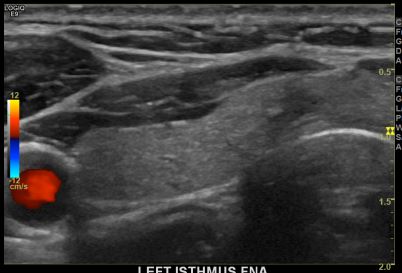

상기환자  외부검사이상소견으로 내원하신 40대 초반 여성분으로 의심스러운 갑상선 결절 세포검사진행후 갑상선암으로 진단되었습니다